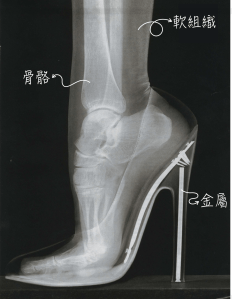

X光片的呈像原理是利用人體組織間對輻射吸收能力不同,因此在成像板上出現不同的黑白對比。例如組織密度比較高的部分,像骨骼、金屬,會在影像上呈現白色;而組織密度比較低的部分,例如軟組織、蛀牙空腔裡空氣,會在影像上呈現黑色。醫師們就以此作為診斷的依據。因爲口腔硬組織佔多數,與其他身體組織相較之下,只需要微小的X光劑量就可以呈像出明顯的對比。尤其目前大多牙科診所X光片已全面數位化,比起傳統影像,更可以使劑量減少數倍。

前面提過,X光片的呈像原理是利用人體組織間對輻射吸收能力不同,因此在成像板上出現不同的黑白對比。例如組織密度比較高的部分,像骨骼、金屬,會在影像上呈現白色;而組織密度比較低的部分,例如軟組織、蛀牙空腔裡空氣,會在影像上呈現黑色。